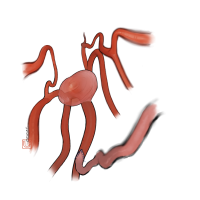

術後イラストシリーズ